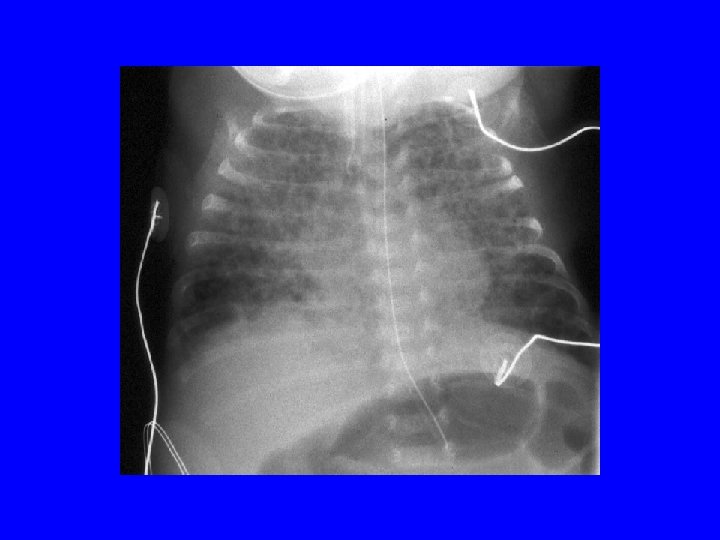

RDS-Surfactant Deficiency • Clinical course: Peak-1 to 3 d and recovery starts with onset of diuresis • Risk Factors: Low GA, male gender , Mat. DM, perinatal depression • RDS in term: SPB def, IDM, Beckwith Weideman syndrome, congenital syphilis • Pathology: Hyaline membrane (cellular debris in fibrinous matrix) • Treatment-surfactant replacement, supportive • Complications: pneumothorax • DD for reticulogranular CXR- GBS pneumonia, PAPVR

Case • An infant is delivered by c/s at 34 wk GA. There is no h/o ROM, maternal fever, or abn. FHR. The infant requires IPPV with a bag-mask and 100% O 2 in the delivery room. AS are 5 and 7. UA p. H was 7. 23. He is admitted to the WBN, but develops respiratory distress within an hour of life. RA ABG shows 7. 10/ 80/50/-10 with CXR

Question 2 • A 28 w GA male infant weighing 1500 g experiences respiratory distress requiring ventilation soon after birth. Ventilator parameters are: SIMV of 40 /min, 22/5 pressures and Fi. O 2 of 0. 8 to maintain a Pa. O 2 of 60 mm Hg. CXR shows. . .